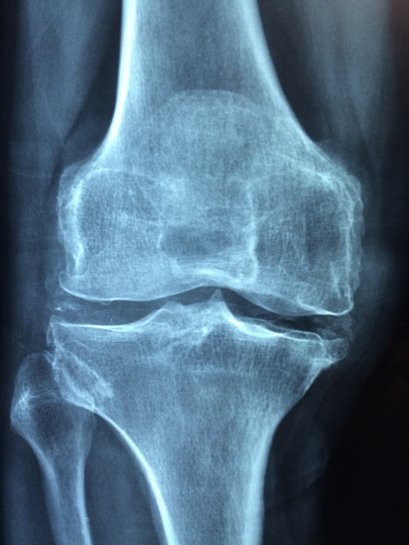

โรคข้อเข่าเสื่อม อันตรายที่ไม่ได้เป็นเฉพาะกับคนแก่เท่านั้น เราจะพาคุณไปทำความรู้จักกับโรคข้อเข่าเสื่อม สาเหตุและการรักษาที่คุณควรรู้เพื่อระวังตัว โรคข้อเข่าเสื่อม ซึ่งเกิดจากกระดูกอ่อนที่คลุมบริเวณปลายข้อต่อของหัวเข่าเสื่อมภาพ

ตอนนี้แม้ยังไม่อาจจะรักษาโรคข้อเข่าเสื่อมให้หายสนิทได้ แต่ก็สามารถควบคุมอาการได้ โดยจุดหมายสำหรับในการรักษาเป็นช่วยทุเลาลักษณะของการปวด ช่วยทำให้ข้อทำงานได้ตามปกติหรือใกล้เคียงภาวะปกติมากที่สุด

คุณมีความเสี่ยงต่อ โรคข้อเข่าเสื่อม มากเพียงใด หากปล่อยไว้นาน ถึงขั้นเดินไม่ได้ ระยะรุนแรงมากน้อยเท่าไหร่ และตัวคุณเองต้องรับรู้ถึงการรักษาอย่างถูกวิธี เพื่อการดำเนินคุณภาพชีวิตได้ตามปกติ